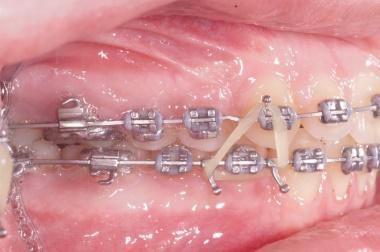

Les accessoires

Les élastiques reliant les dents du haut et les dents du bas seront prescrits par l’orthodontiste, suivant la déformation des mâchoires et la sévérité. Changez vos élastiques au moins une fois par jour, ils ont tendance à se détériorer et perdre leur force après 24 heures.

Les propulseurs permettent de corriger les déformations sévères avec un maximum d’efficacité ce sont des accélérateurs de croissance , ils sont fixes sur les bagues pendant 3 mois puis sont enlevés pour être remplacés par des élastiques.